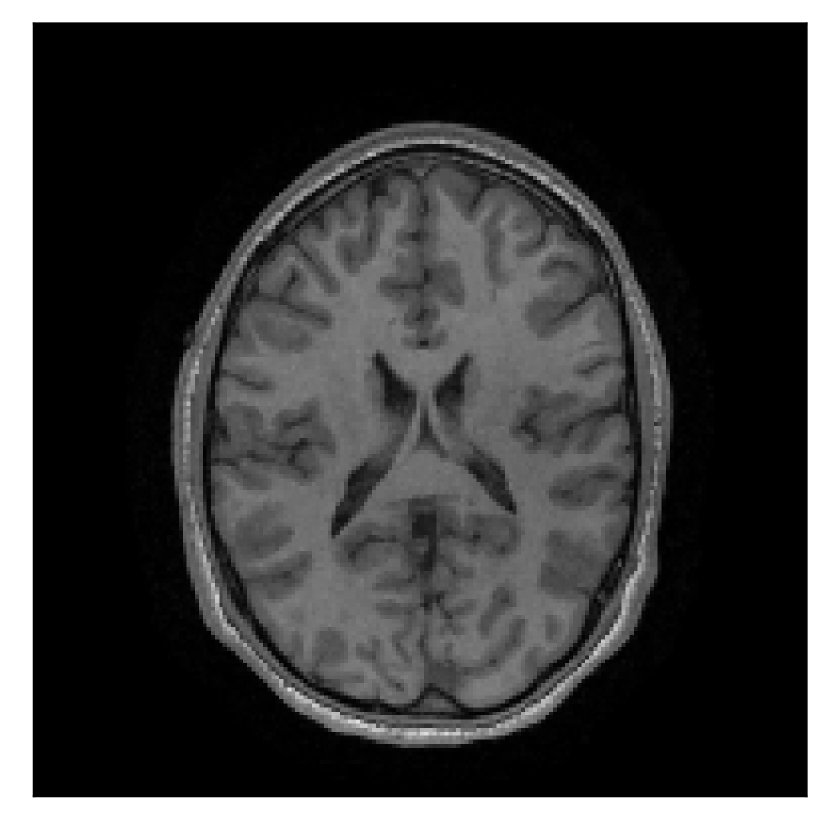

We consider three levels of motion corruption: (i) the volunteer moves once, (ii) the volunteer moves twice, and (iii) the volunteer moves five times. The volunteer is instructed to change its head position every time it is prompted to do so, and maintain that position in between instructions. We use T2-FLAIR-weighted contrasts as corrupted scans, with T1-weighted contrast as a reference (see Table 1 for further details). The corrupted acquisition employs randomized sampling.

4.1 Experiment 1: robustness test

We gather the results for the robustness test described in Section 3.1 (volunteer 1) in Figures 2, 4, and 6 for motion corruption mechanisms associated to one, two, and five changes of position, respectively. Furthermore, we juxtapose the corrected images with varying degrees of corruption in Figure 8. We observe that the proposed method consistently ameliorates the corrupted scan. The quality indexes based on PSNR and SSIM show only a modest decrease in correction quality as a function of motion complexity (Figure 8).

| Section 3.1, Figure 2 | Sagittal | 23.94 | 27.95 | 0.7068 | 0.7936 |

| Coronal | 26.66 | 29.82 | 0.7653 | 0.8332 | |

| Axial | 25.40 | 30.16 | 0.7616 | 0.8490 | |

| Section 3.1, Figure 2 | T2-FLAIR | Completely corrected | Some blurring | No additional artifacts | Good grey white matter differentiation |